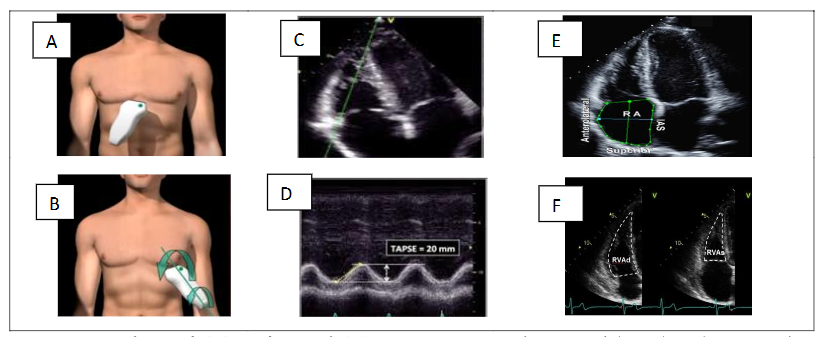

STEP 4 – DE ESTIMATION OF TRICUSPID ANNULAR PLANE SYSTOLIC EXCURSION (TAPSE), RIGHT ATRIAL (RA) SIZE AND QUALITATIVE ASSESSMENT OF RIGHT VENTRICULAR STRUCTURE AND FUNCTION

a. Tricuspid Annular Plane Systolic Excursion (TAPSE)

TAPSE is an angle-dependent measurement. Therefore, it is important to align the M-mode cursor along the direction of the lateral tricuspid annulus. Select a fast sweep speed. The excursion of the lateral tricuspid annulus is measured in M-mode between the end of diastole and the peak of systole and is a measure of the longitudinal systolic function of the RV in the apical four-chamber view. TAPSE < 1.7 cm is highly suggestive of systolic dysfunction of the RV.

b. Right atrial (RA) dimensions

Area is measured in the apical four-chamber view at end-systole (normal values ≤ 18 cm²), on the frame just prior to tricuspid valve opening, by tracing the RA blood-tissue interface, excluding the area under the tricuspid valve annulus. RA dilatation usually indicates exposure to chronic elevations in RA pressure due to tricuspid valve disease or increased right ventricular filling pressure.

c. Right ventricular (RV) dimensions, right to left ventricular ratio and pericardial effusion

Due to the increasing preload and afterload, there is progressive right ventricular dilatation with worsening PH. All measurements are taken at the end of diastole in the right ventricular-focused view. When performing the methods to quantify right atrial and ventricular size, it is important to pay attention to the correct timing of the cardiac cycle.

Measure the right ventricular at the end of diastole—when it is at its widest. The volume for the right atrial is measured at the end of systole, when it is at its largest volume. It is also possible to evaluate right ventricular-left ventricular ratio, size, and total left ventricular circumference, which, albeit in a generalized form, allows assessment of contractile efficiency and, in the context of the COPD hypothesis, vascular and cardiopulmonary phenotyping. The measurement is performed in apical view without foreshortening and is taken at the end of diastole. A ratio of >1 at the end of diastole suggests right ventricular dilatation. The presence of a pericardial effusion due to PH is a sign of advanced disease with a poor prognosis.

d. Fractional Area Change (FAC)

Fractional Area Change (FAC) is measured in apical four-chamber manual tracing of the RV endocardial border from the lateral tricuspid annulus along the free wall to the apex and back along the interventricular septum to the medial tricuspid annulus at the end of diastole and at the end of systole. A disadvantage of this measure is that it neglects the contribution of the RV outflow tract to overall systolic function. An RV FAC < 35% indicates systolic dysfunction of the RV (figure 4).

Figure 4. Subcostal (A) and apical (B) views. Decreased tricuspid annular plane systolic excursion (TAPSE) (C–D); end-systolic RA area (E); RV FAC Fractional Area Change (F).